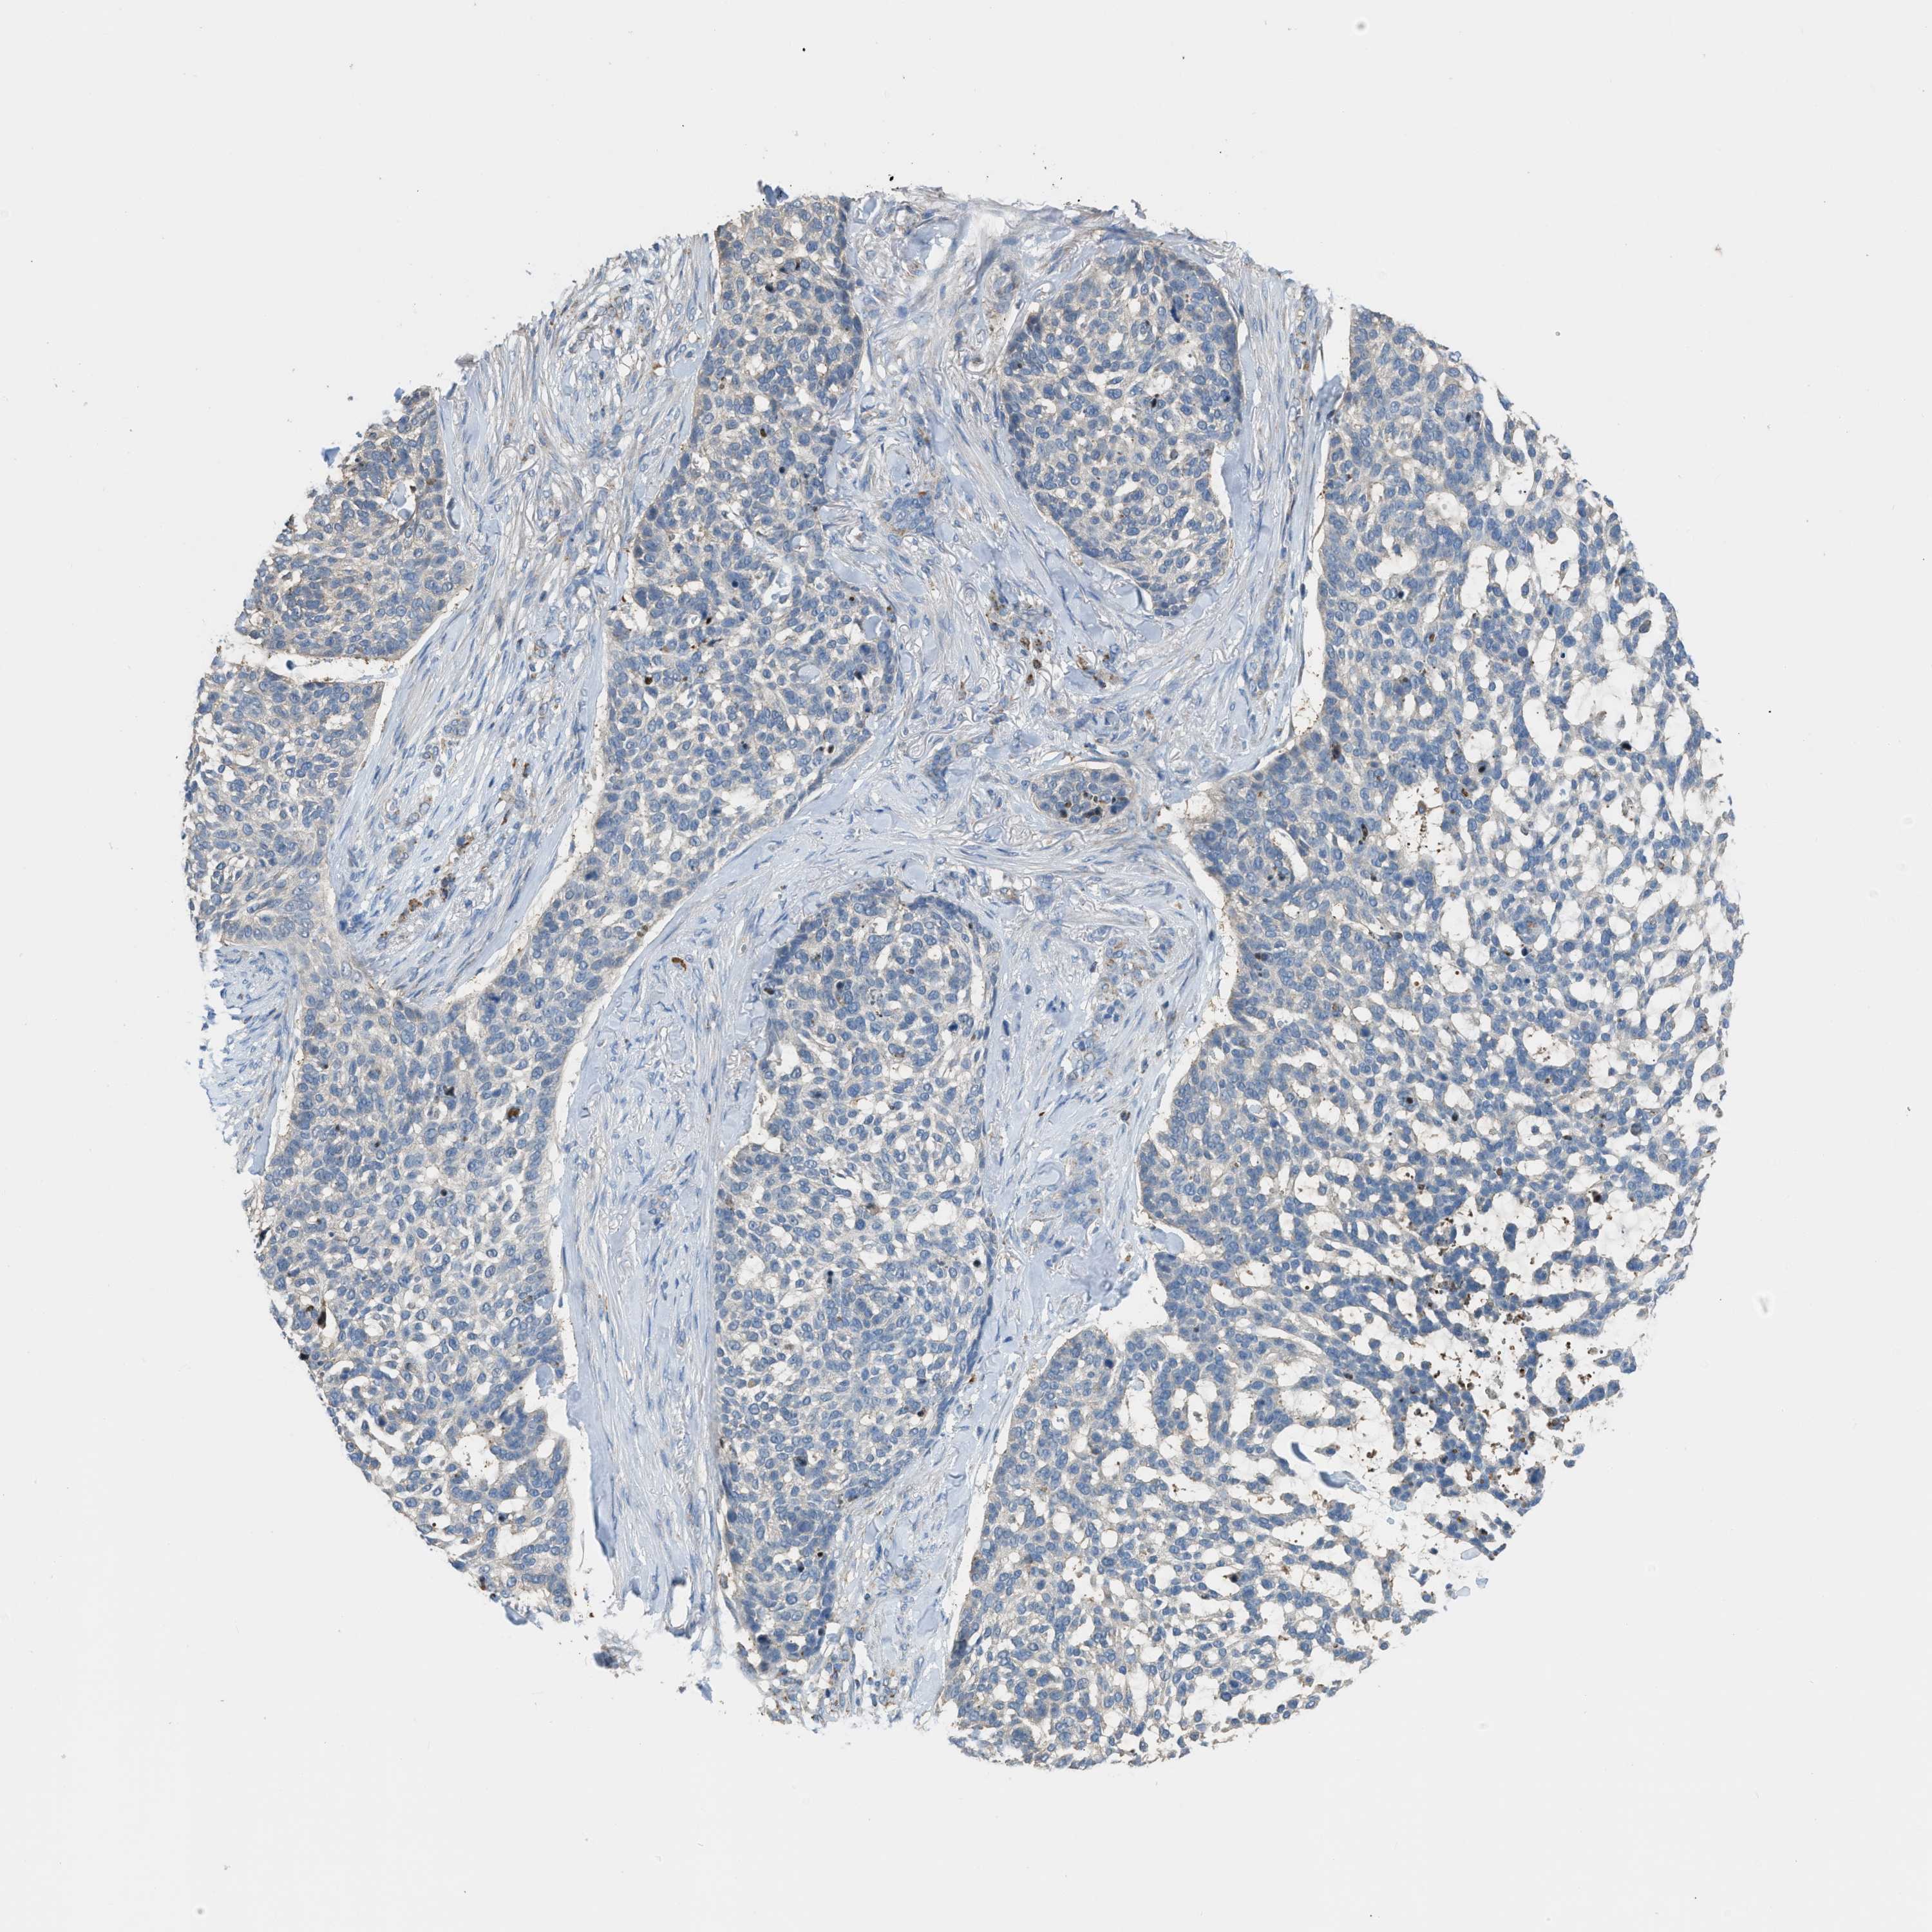

SKIN CANCER - Protein expressioni

A mouse-over function shows sample information and annotation data. Click on an image to view it in a full screen mode. Samples can be filtered based on level of antibody staining by selecting one or several of the following categories: high, medium, low and not detected. The assay and annotation is described here.

Each image is clickable and will lead to virtual microscopy that enables deeper exploration of all samples and also displays staining intensity scores, fraction scores and subcellular localization as well as patient and tissue information for each sample.

Antibody HPA018923

Squamous cell carcinoma, metastatic, NOS